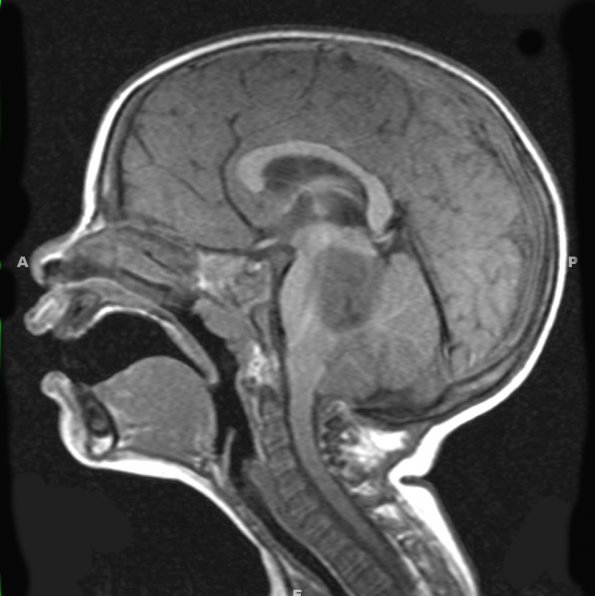

Case 2 History ---- The patient was a 2 year-old boy with a history of torticollis, ataxia, and right hemiparesis. He had a large mass at the left posterior aspect of the pons/midbrain with invasion of the left cerebellum and effacement of the 4th ventricle. Operative procedure: Craniotomy with resection of posterior fossa tumor. ---- 2A1-3 MRI Studies ---- A1,2 The tumor is hypointense in this T1-weighted sagittal section (2A1) involving the brainstem and cerebellum and does not enhance with contrast (2A2).